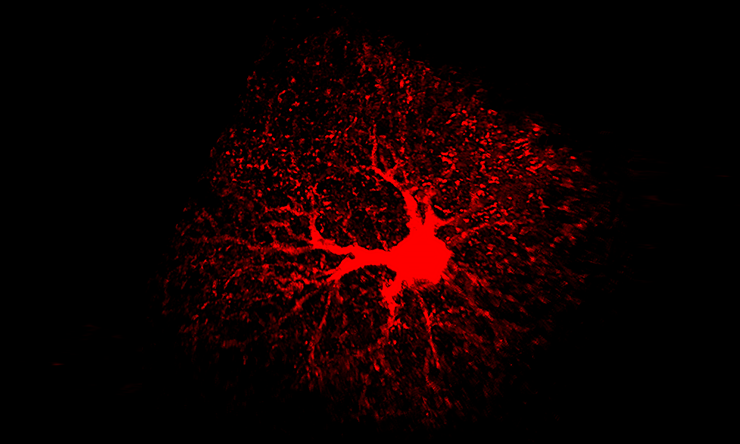

The researchers worked with a mouse model they had genetically engineered to lack the NFIA gene specifically in adult astrocytes in the entire brain. They analyzed several brain regions, looking for alterations in astrocyte morphology, physiology and gene expression signatures.

“We found that NFIA-deficient astrocytes presented defective shapes and altered functions,” said Deneen, who holds the Dr. Russell J. and Marian K. Blattner Chair and is a member of the Dan L Duncan Comprehensive Cancer Center at Baylor. “Surprisingly, although the NFIA gene was eliminated in all brain regions, only the astrocytes in the hippocampus were severely altered. Other regions, such as the cortex and the brain stem, were not affected.”

Astrocytes in the hippocampus also had less calcium activity – calcium is an indicator of astrocyte function – as well as a reduced ability to detect neurotransmitters released from neurons. NFIA-deficient astrocytes also were not as closely associated with neurons as normal astrocytes.